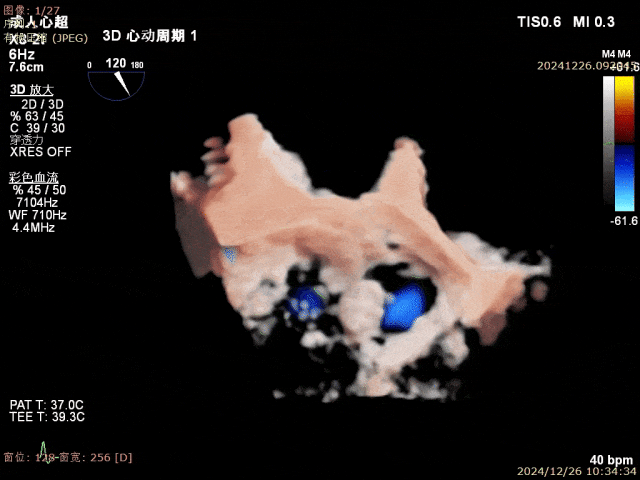

患者为68岁男性,3月前出现气短,活动后明显,休息可缓解,无明显胸痛,无夜间呼吸困难,就诊当地医院考虑“肺炎、心衰”,给予对症治疗好转,具体不详,无明显发热,无咳嗽咳痰,出院后未规律服药。10天前,气短再发,就诊当地医院心脏彩超提示二尖瓣后叶腱索断裂,二尖瓣关闭不全伴重度反流。左心增大,室间隔增厚,肺动脉高压,三尖瓣轻度反流,主动脉瓣中度反流。心电图提示房颤,左室肥大。为进一步诊治入院。经食道超声提示:患者二尖瓣后叶脱垂伴腱索断裂,前叶2.6cm,后叶1.4cm,脱垂宽度16mm,脱垂高度8mm,瓣口面积6.0cm²。

术前影像